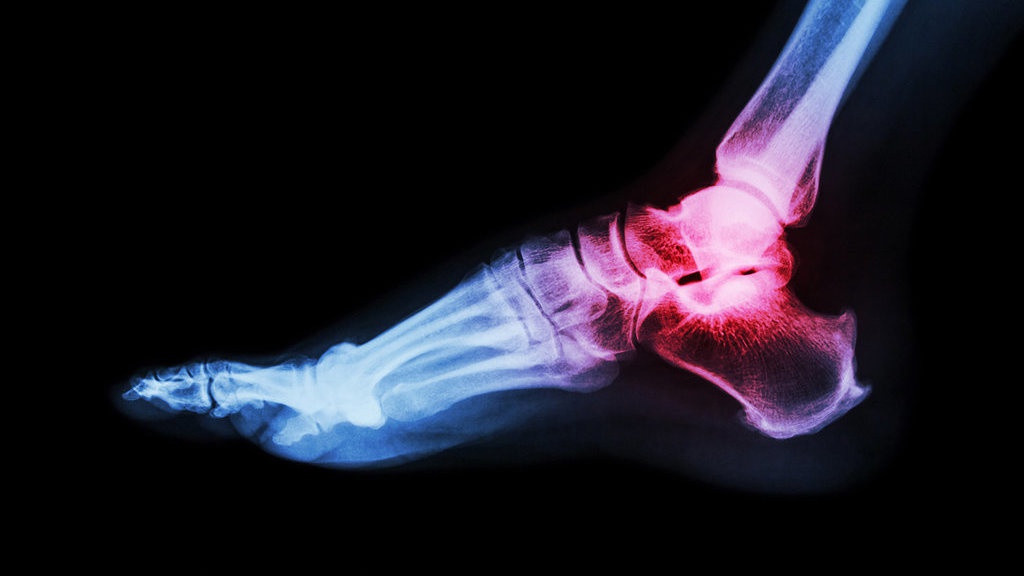

Penyakit rematik atau biasa disebut Rheumatoid Arthritis (RA) biasanya ditandai dengan mengalami kaku pada sendi di pergelangan tangan, lutut, atau tangan terutama pada pagi hari.

Laman Healthline menyebutkan, kekakuan dan peradangan sendi ini disertai dengan rasa nyeri, panas, dan biasanya disertai dengan pembengkakan pada bagian yang terkena.